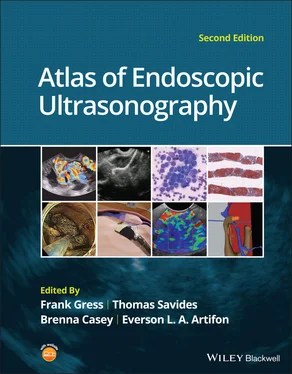

Figure 2.1shows the esophageal walls using radial and linear instruments. To help separate the layers, these images include a muscularis mucosae leiomyoma that was subsequently resected. Images show subepithelial hypoechoic lesion in echolayer II as well as in the other defined layers of the esophageal wall.

Figure 2.1 (a) Radial array image of esophageal wall with small echolayer II leiomyoma. (b) Linear array image of esophageal wall with small echolayer II leiomyoma.